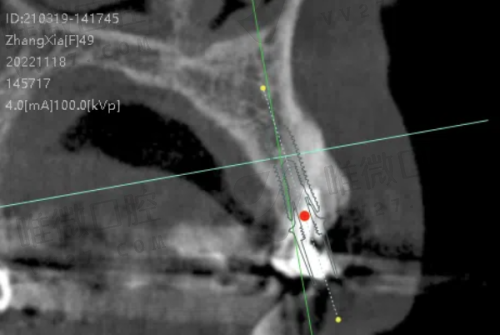

除了医生厉害,医院的设备咱也不能马虎。定靖口腔医院的设备可不是“凑合用”,而是非常现代化的。比如,医院目前配备了8台口腔综合治疗机、韩国怡友口腔全景影像设备、美国的根管测量仪与根管马达、德国进口的卡瓦光敏固化设备等等。

这些高端设备的加入,使得常规的拔牙、补牙到牙齿种植、正畸矫正治疗都变得更加效率高、精细和舒适。尤其是在进行根管治疗或者数字化正畸时,精良的设备真的能让你少遭不少罪。

尤其是他们家的数字化种植技术和活动义齿定制服务,已经逐渐成为区域内的小标杆。通过3D数字口扫+导板种植技术,不仅快捷、正确,还减少术后不适,是不少中老年患者的优选之一。